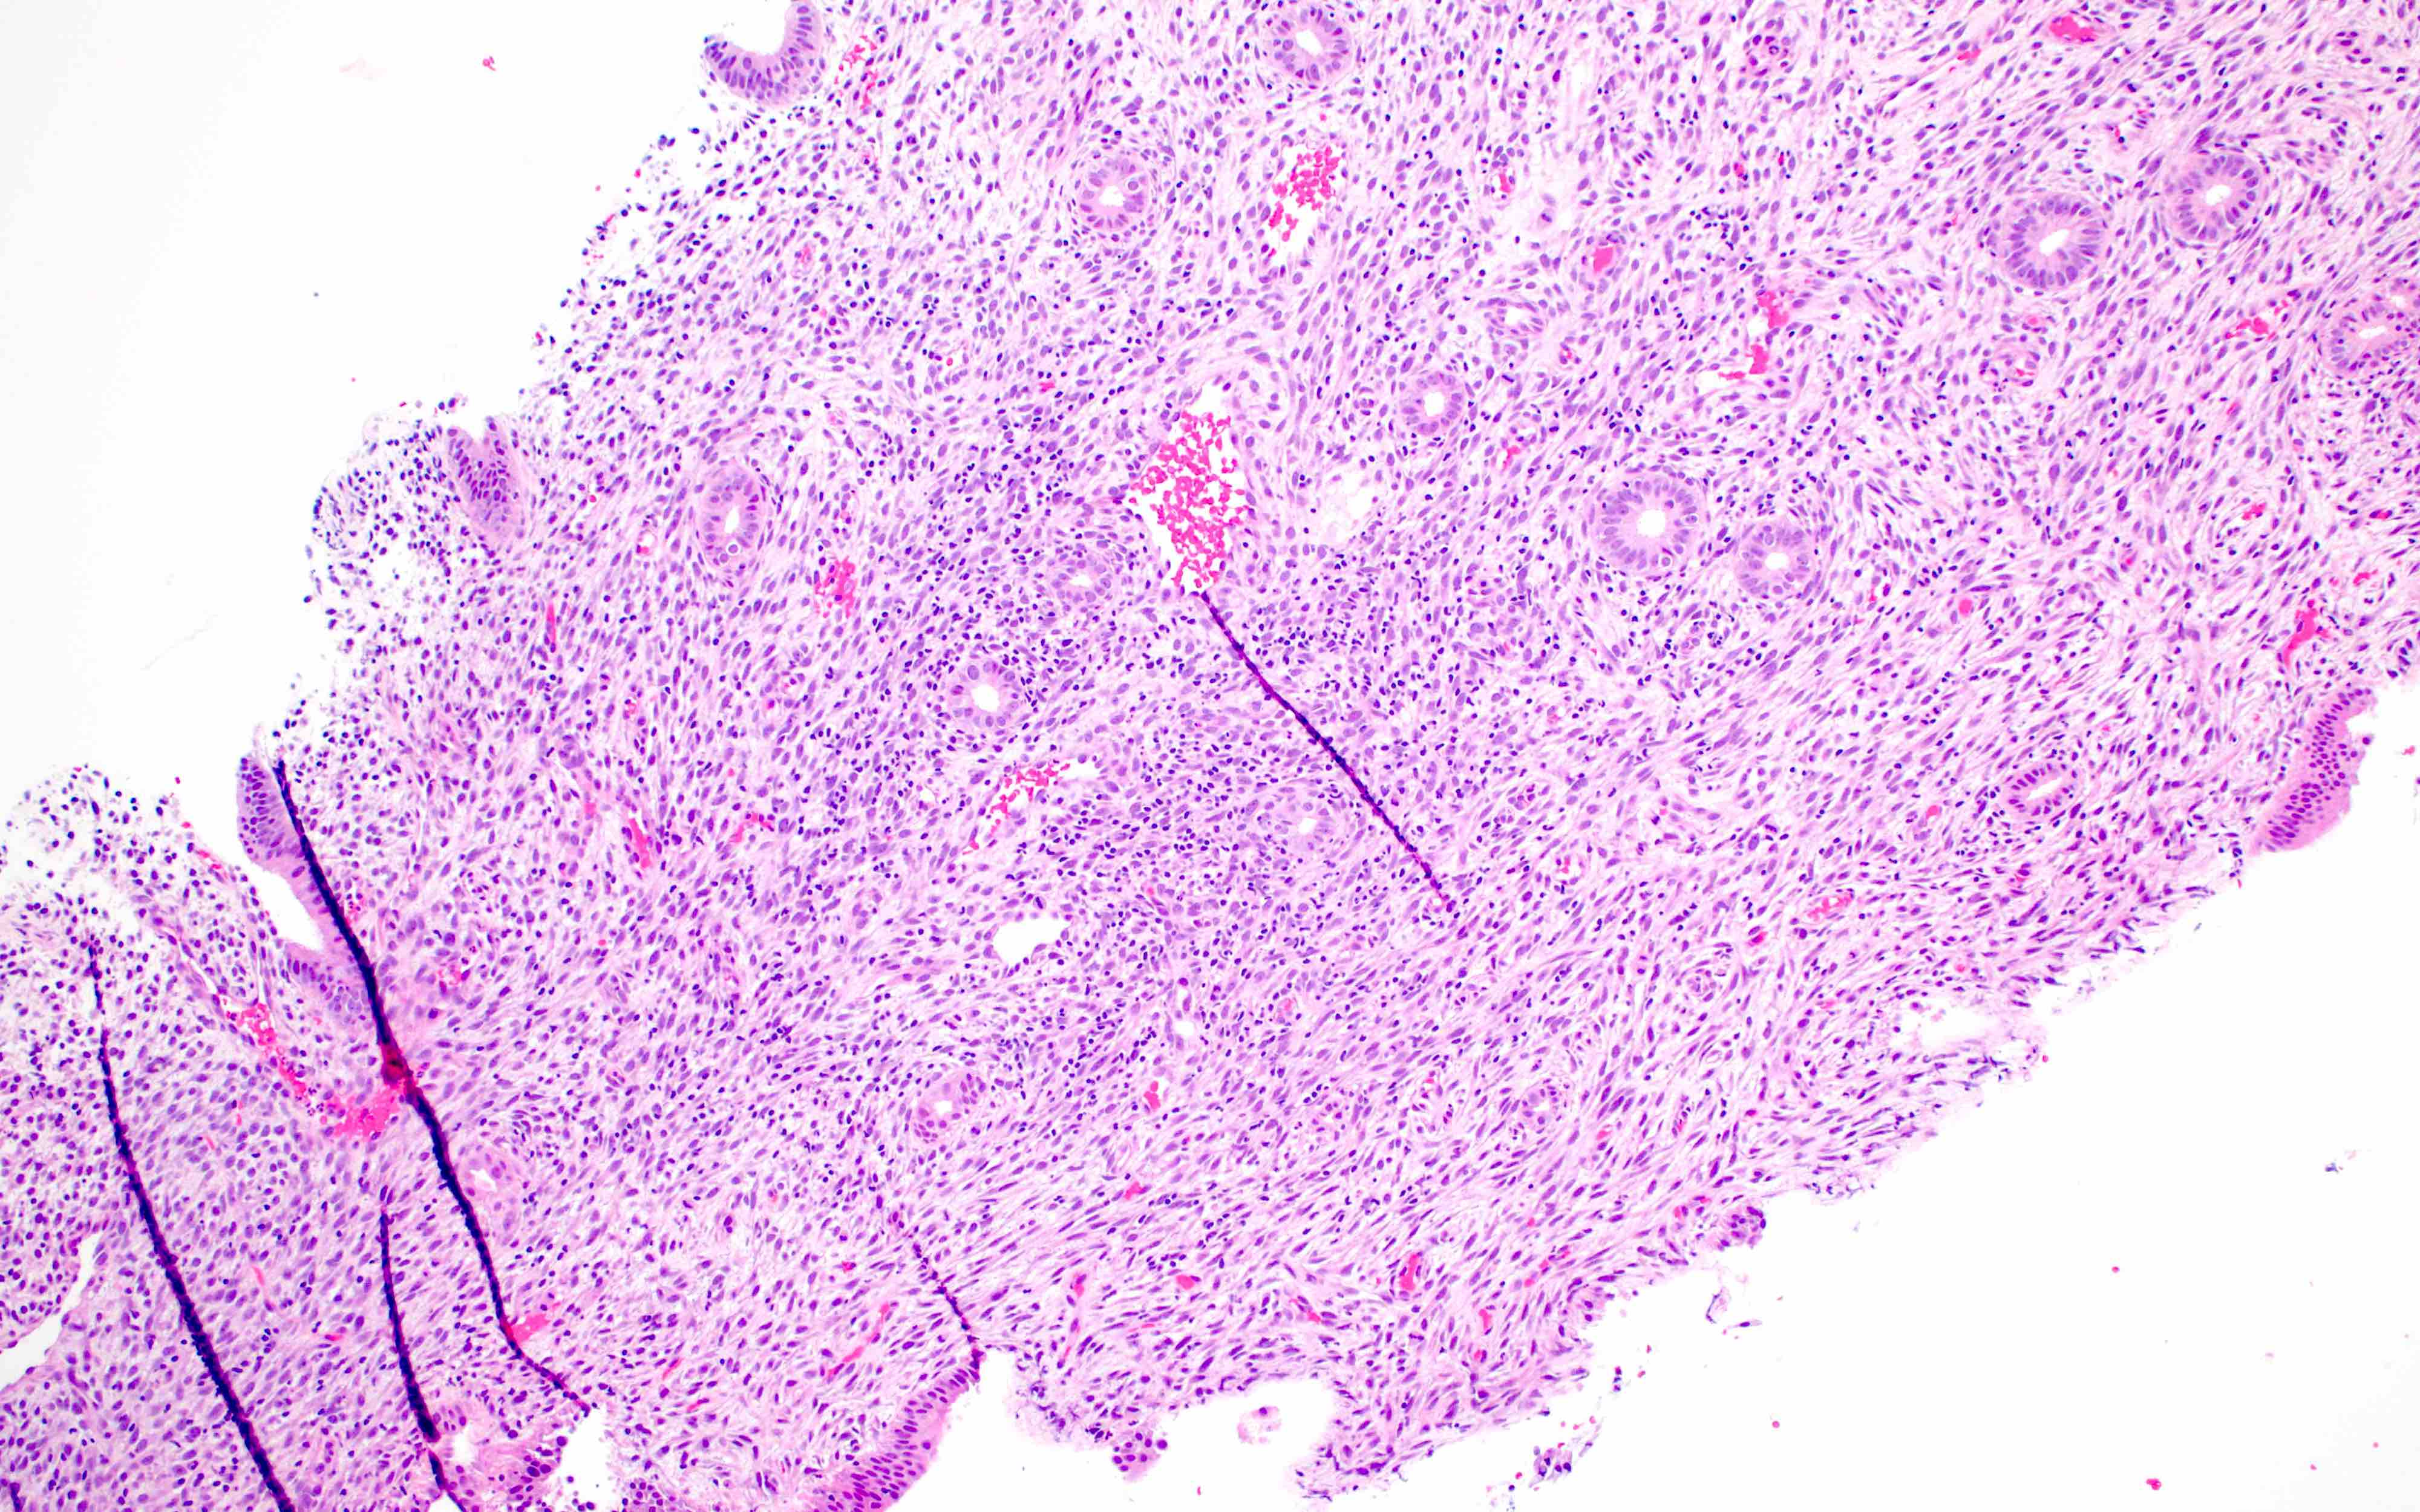

- Xanthogranulomatous endometritis

- Abundant foamy histiocytes, siderophages, neutrophils, plasma cells, lymphocytes

- With or without fibrosis, calcification

Microscopic (histologic) images

Contributed by Stephanie L. Skala, M.D. and Yuri Tachibana, M.D.

Chronic endometritis

Xanthogranulomatous endometritis